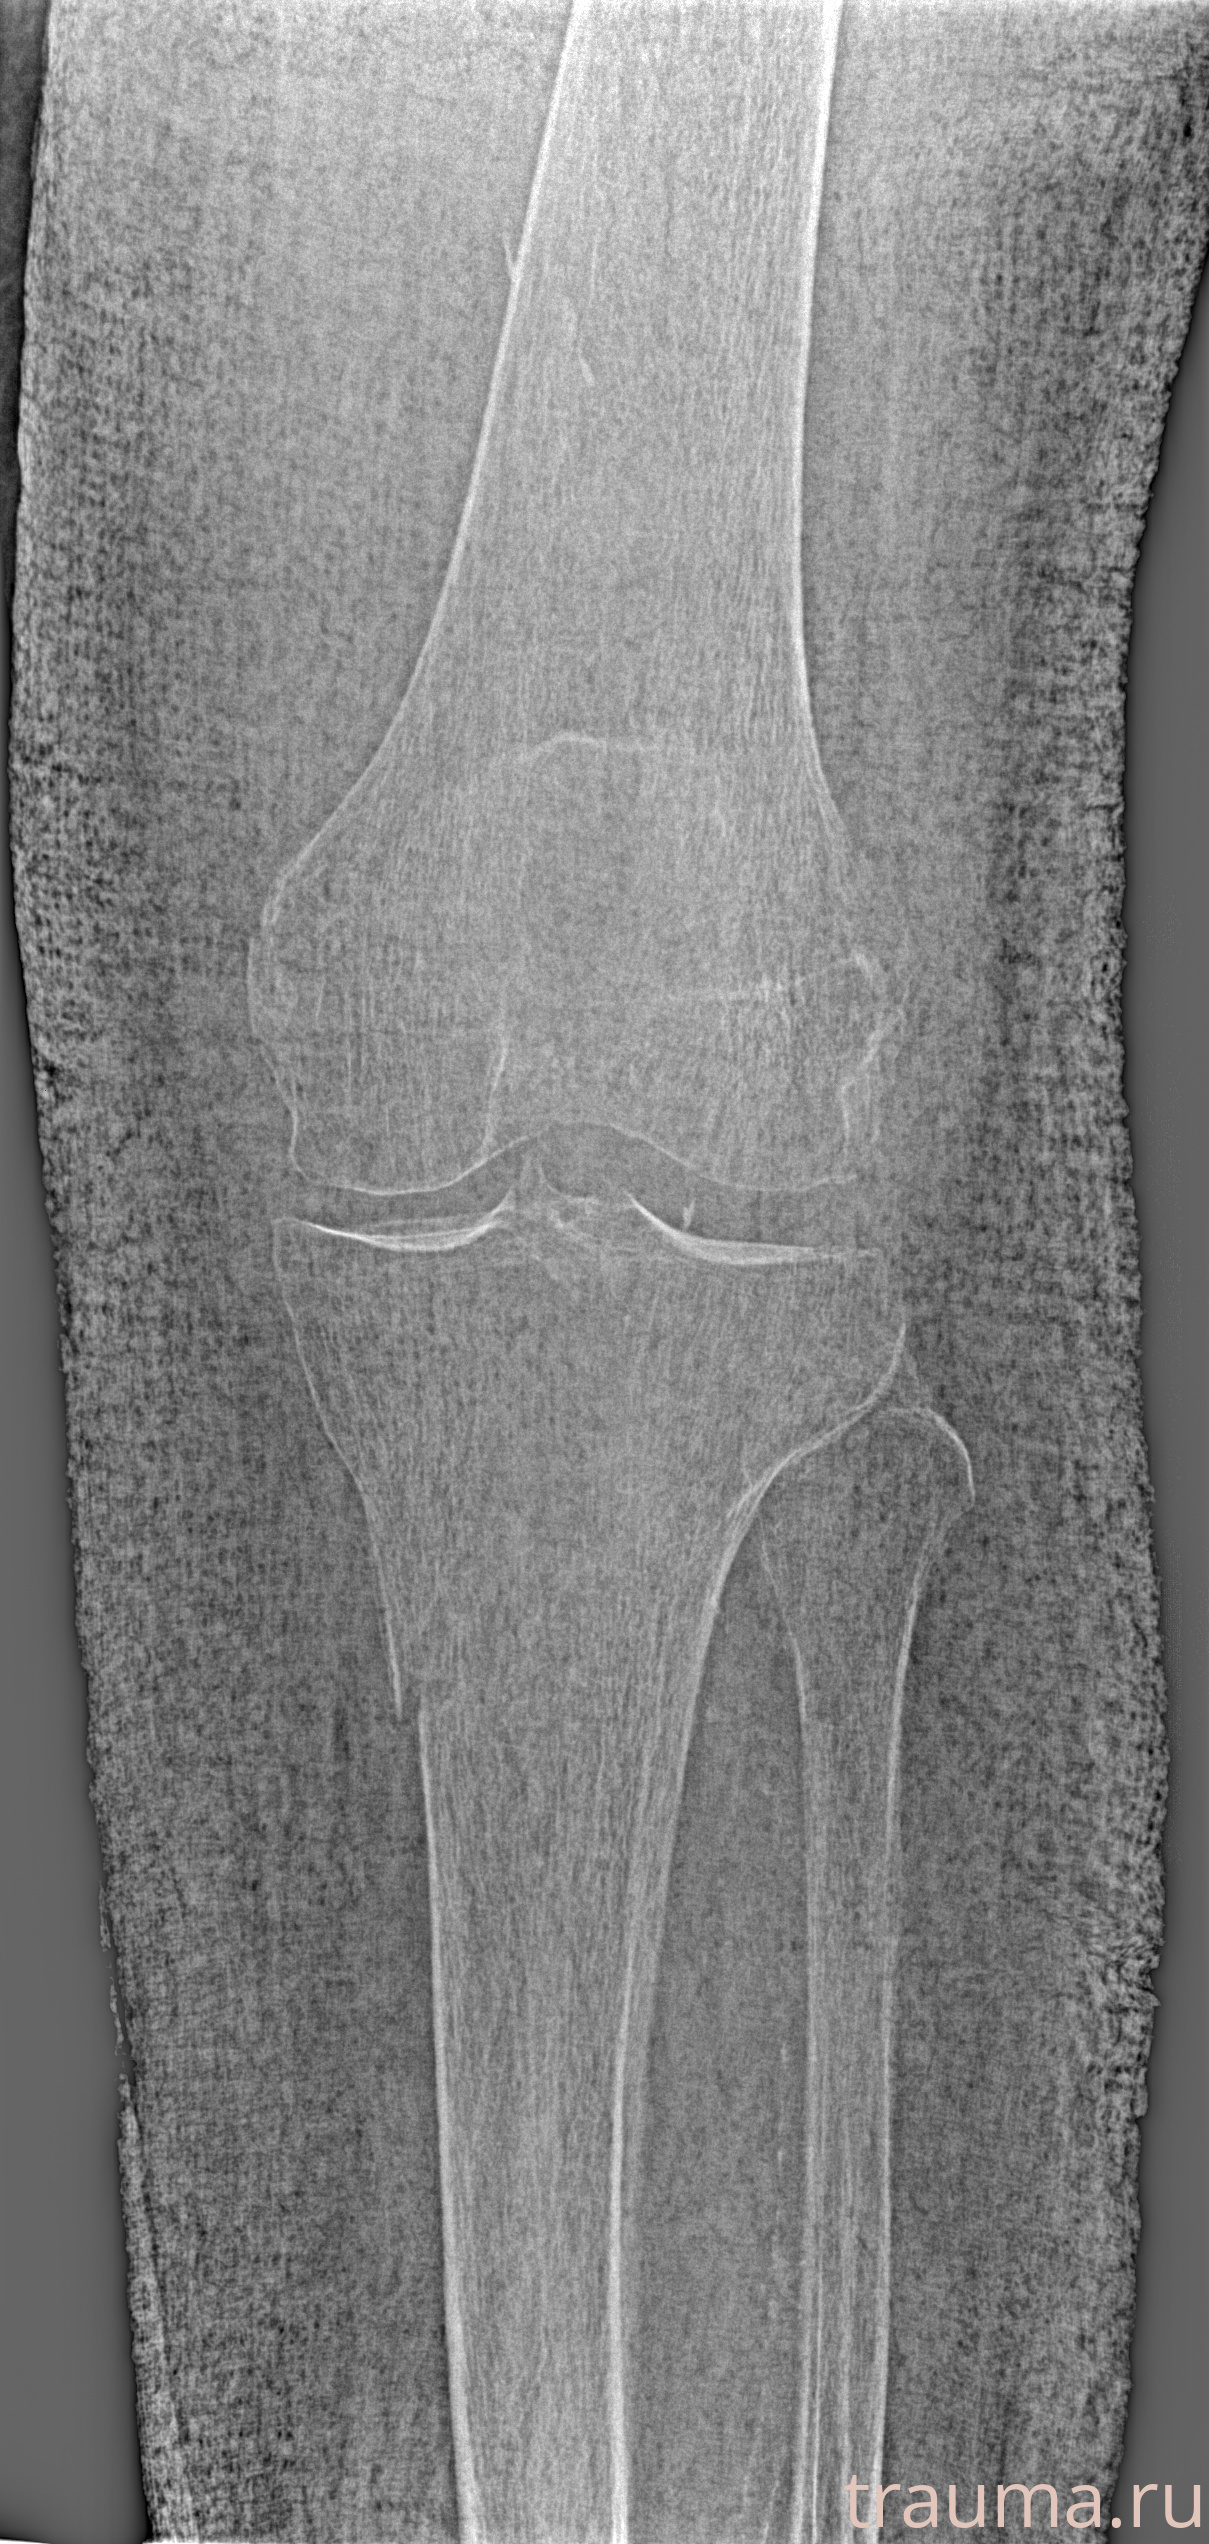

Рентгенограммы

Рентген на дому: по вашему адресу приезжает врач-рентгенолог, травматолог-ортопед с мобильным рентгеновским аппаратом, проводит диагностику травмы или заболевания, делает необходимые рентгенограммы, дает рекомендации по дальнейшему лечению. Получить качественные снимки в домашних условиях возможно благодаря уникальной методике, разработанной МосРентген Центром для института  Склифосовского